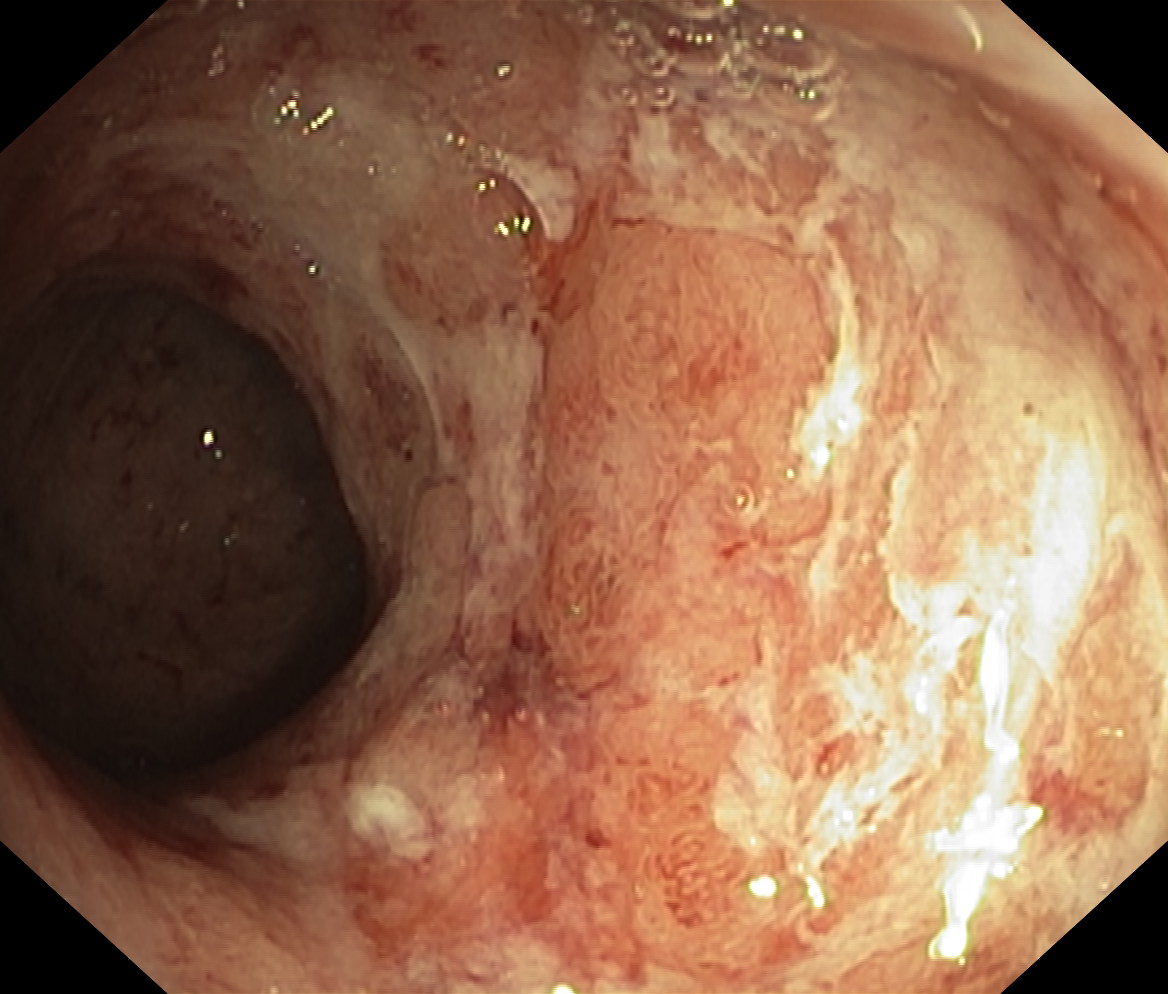

Zapalenie wrzodziejące...

Zapalenie wrzodziejące jelita grubego